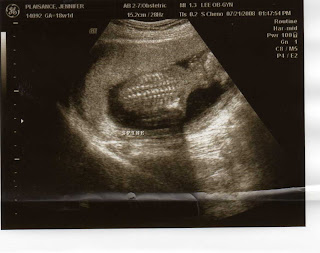

We had our routine ultrasound July 21st. It's taken me awhile to post about it...and thanks to Alyssa, here are a couple of pictures! We are so thankful that everything looked great and the baby is healthy. We did not find out the gender...we loved not knowing with William, so you will have to love waiting with us!"For you created my inmost being;